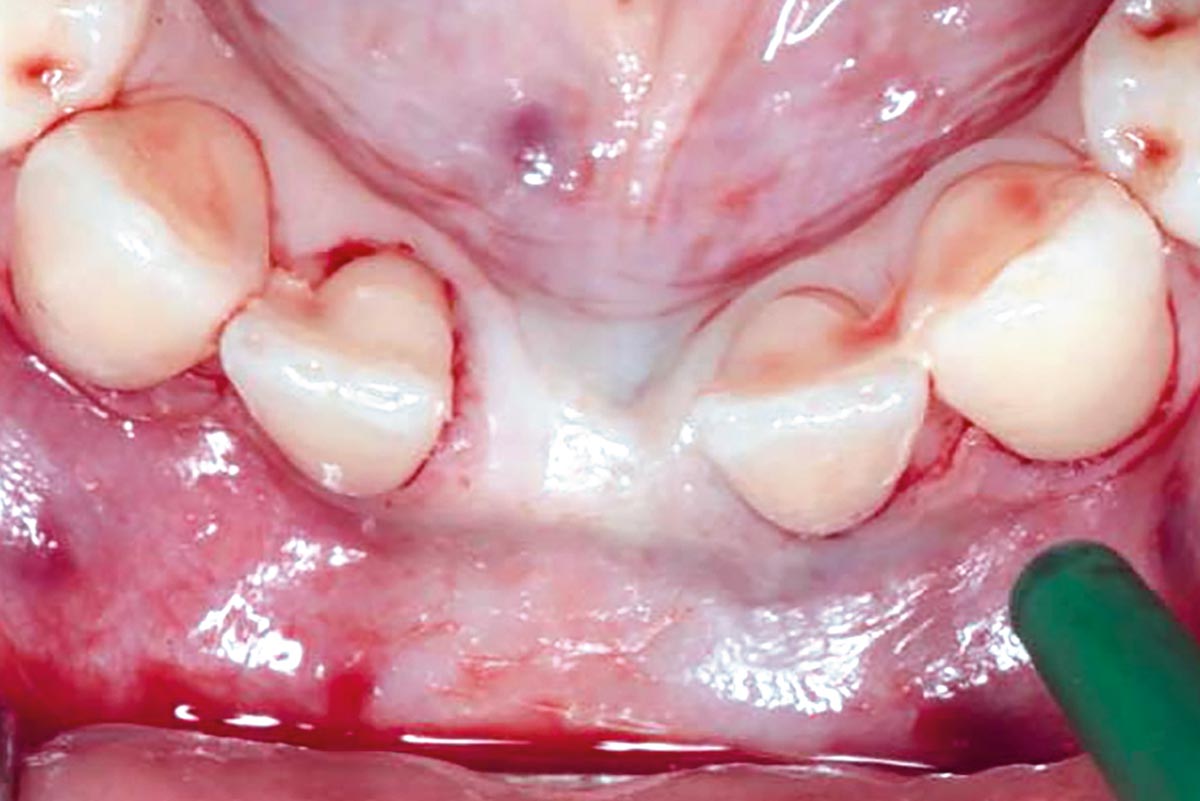

Regenerative corticotomy to compensate lower incisor malocclusion with cerabone® and mucoderm®

Initial view of the clinical case: Class III malocclusion

Treatment plan: Regenerative corticotomy (PAOO)